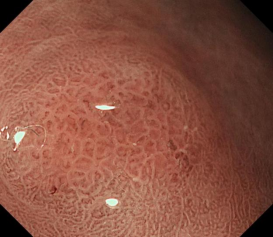

科室高清晰胃肠镜:正常的胃窦(线圈样腺管)和食管粘膜放大观察(IPCL)